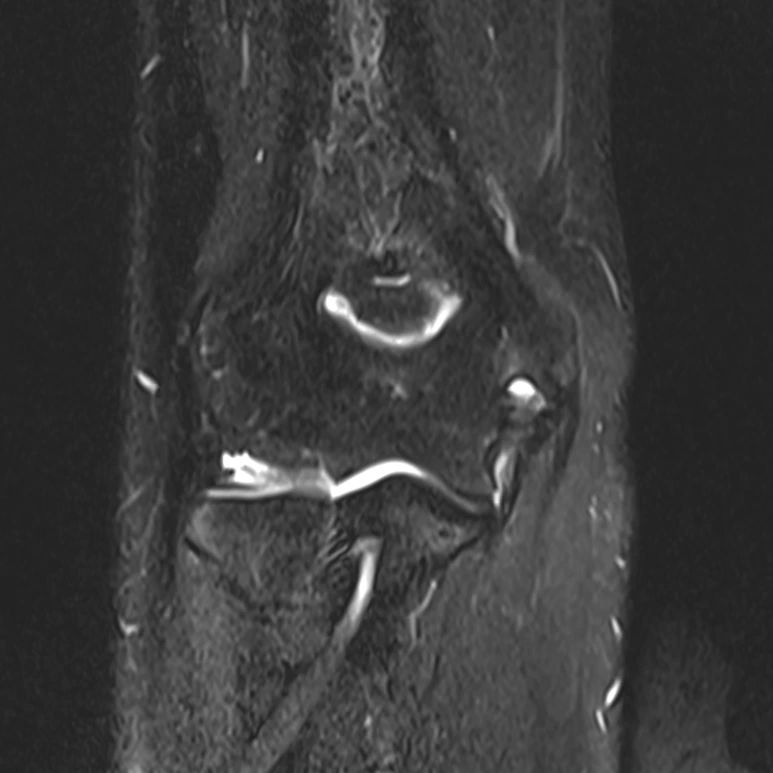

그럼 환자의 MRI 사진을 한번 보겠습니다.

우측 부위의 측부 인대 부위에 손상이 있는 것이 눈으로 보이실까요? 해당 부위의 손상은 부분 파열로 수술을 선택해도 되고 안해도 됩니다. 일반인의 경우에는 수술을 선택하지 않습니다. 그리고 조만간 프로 지명을 앞두고 있으며, 단기간에 몸을 쓸 일이 있다면 비수술 재활을 선택하게 됩니다. 그러나 앞으로 프로 지명까지 시간이 많이 남아 있으며 완벽하게 구조적인 안정성을 만들고 계속 운동하고 싶다면 수술을 선택하기도 합니다.

환자는 MRI 촬영 이후 팔꿈치 내측측부인대의 파열을 발견하여 수술을 결정하였습니다. 김진섭 병원에서 수술을 시행하였으며 그 뒤로 수술 후 재활을 위해서 내원한 환자입니다. 약 1달간의 재활을 하였으며, 통증 부위의 유착을 방지하고, 수술 후 조직 재생을 돕기 위한 한약치료, 침치료, 뜸치료, 봉침치료를 시행하였으며 조기 복귀를 위한 스포츠 재활도 시행하였습니다. 열린사슬 운동부터 시작해서 닫힌사슬 운동까지 현재는 체중부하 운동까지 가능하게 되었습니다.